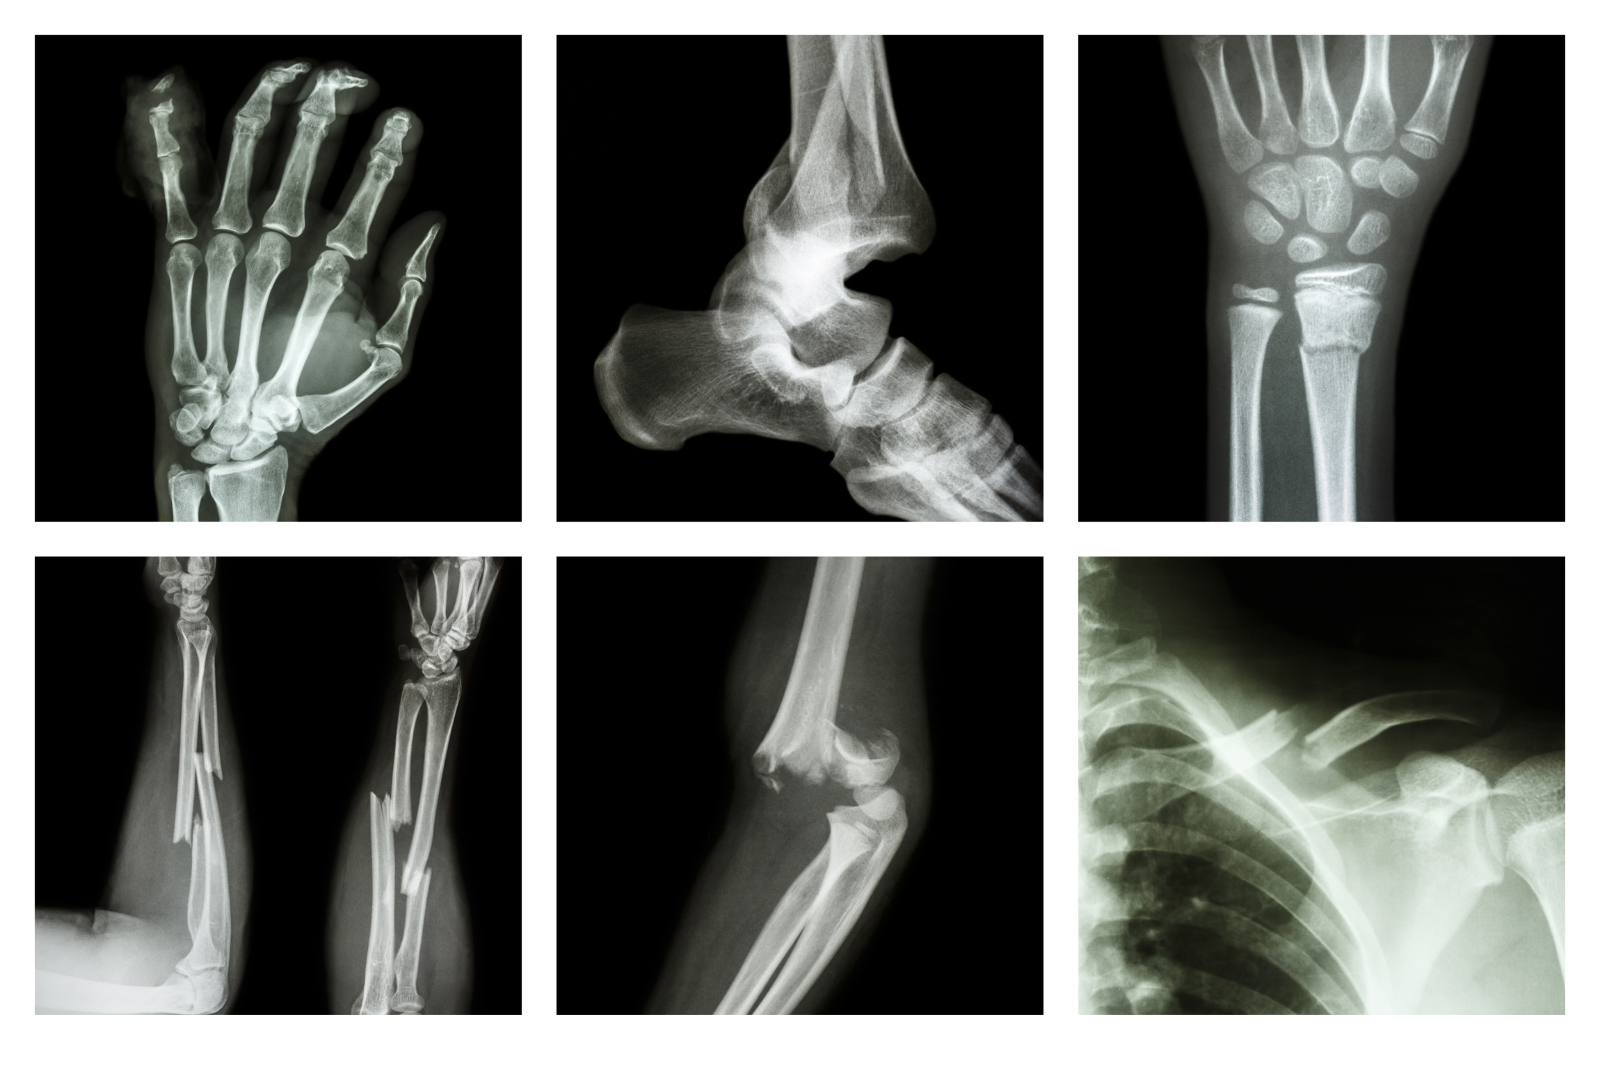

Fiksimi i kockës: Çfarë do të thotë, kur është i nevojshëm dhe si zhvillohet rikuperimi

Fiksimi i kockës është një procedurë mjekësore që përdoret për të bashkuar në mënyrë të qëndrueshme një kockë të thyer ose të dëmtuar, me qëllim që të shërohet siç duhet. Mund të jetë i brendshëm ose i jashtëm dhe aplikohet në lloje të ndryshme frakturash ose ndërhyrjesh kirurgjikale.

Llojet më të zakonshme të frakturave dhe koha e pritshme e rikuperimit

1. Frakturë e ijeve (hip fracture)

• Shfaqet kryesisht te të moshuarit (veçanërisht gratë me osteoporozë)

• Kërkon fiksim kirurgjikal me vida ose zëvendësim të nyjës (endoprotezë)

• Rikuperimi: 3–6 muaj, me fizioterapi dhe ndihmë për ecje (shëtitëse/shtiza)

2. Frakturë e kyçit të dorës (distal radius fracture)

• Shfaqet te personat që bien mbi dorën e shtrirë

• Trajtimi më i zakonshëm: allçi ose pllakë me vida

• Rikuperimi: 6–8 javë, me rikthim të plotë të lëvizshmërisë përmes ushtrimeve

3. Frakturë e kyçit të këmbës

• Shfaqet te të rinjtë aktivë, sportistët

• Trajtimi varet nga stabiliteti; ndonjëherë kërkohet fiksim i brendshëm

• Rikuperimi: 8–12 javë

4. Frakturë e femurit (kocka e kofshës)

• Trajtimi: fiksim i brendshëm me shufër ose pllakë

• Rikuperimi: 4–6 muaj me rehabilitim intensiv dhe të gradualshëm

• Kontroll mjekësor dhe imazheri (rreze X, CT, MRI)